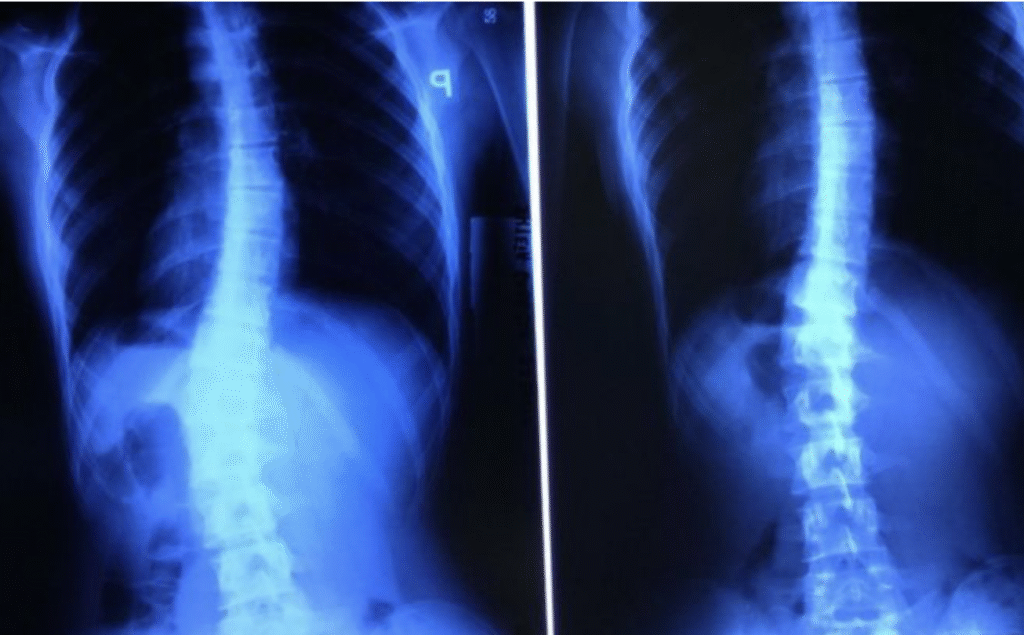

Maciej – 7 lat

Skolioza jednołukowa (statyczna) – zdj. z lewej. Korekcja uzyskana w trakcie jednej wizyty – zdj. z prawej